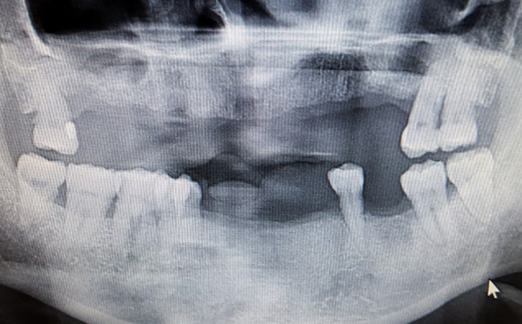

Implants vs. Dental Bridges

• Natural Replacement: Implants provide a more natural and cost-effective solution compared to bridges, which involve altering healthy teeth.

• Longevity: While bridges may last 5-10 years, implants offer a lifetime of functionality and durability.

(13 years After Placement)

“Dental implants prevent bone loss and preserve jaw strength and aesthetics.”

“Dental bridges risk gum disease, jaw shrinkage, and aging effects like wrinkles and bridge loss.”